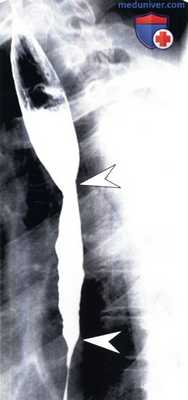

(Слева) На рисунке показаны таблетки, которые не смогли пройти по пищеводу и остановились на уровне аортального сужения. Проиллюстрирован спазм прилежащих отделов пищевода, а также язвы.

(Справа) На рентгенограмме пищевода определяется широкая, неглубокая язва на уровне дуги аорты. У пациента имелись жалобы на боль во время глотания; недавно он принимал внутрь тетрациклин. Через некоторое время симптомы самопроизвольно исчезли. Физиологические сужения пищевода, расположенные на уровне дуги аорты и ретрокардиально, чаще всего поражаются при контакте с лекарственными препаратами. (Слева) На рентгенограмме пищевода, полученной в ходе рентгеноскопии с двойным контрастированием у женщины 50 лет с жалобами на боль при глотании при приеме тетрациклина, визуализируются множественные язвы и умеренно выраженная стриктура (или спазм) дистального отдела пищевода.